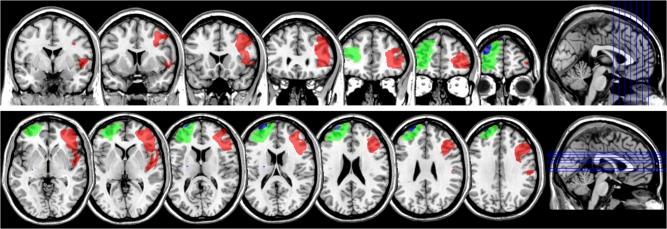

Distinct Roles for the Anterior Cingulate and Dorsolateral Prefrontal Cortices During Conflict Between Abstract Rules.

Distinct patterns of activity within the anterior cingulate cortex (ACC) and dorsolateral prefrontal cortex (dlPFC) reported in neuroimaging studies during tasks involving conflict between competing responses have often been cited as evidence for their key contributions to conflict-monitoring and behavioral adaptation, respectively. However, supporting evidence from neuropsychological patients has been scarce and contradictory. We administered a well-studied analog of the Wisconsin Card Sorting Test, designed to elicit conflict between 2 abstract rules, to a cohort of 6 patients with damage to ACC or dlPFC. Patients who had sustained more significant damage to the ACC were not impaired either on a measure of "conflict cost" nor on measures of "conflict-induced behavioral adaptation." In contrast, damage to dlPFC did not affect the conflict cost measure but abolished the patients' ability to adapt their behavior following exposure to conflict, compared with controls. This pattern of results complements the findings from nonhuman primates with more circumscribed lesions to ACC or dlPFC on the same task and provides converging evidence that ACC is not necessary for performance when conflict is elicited between 2 abstract rules, whereas dlPFC plays a fundamental role in behavioral adaptation.